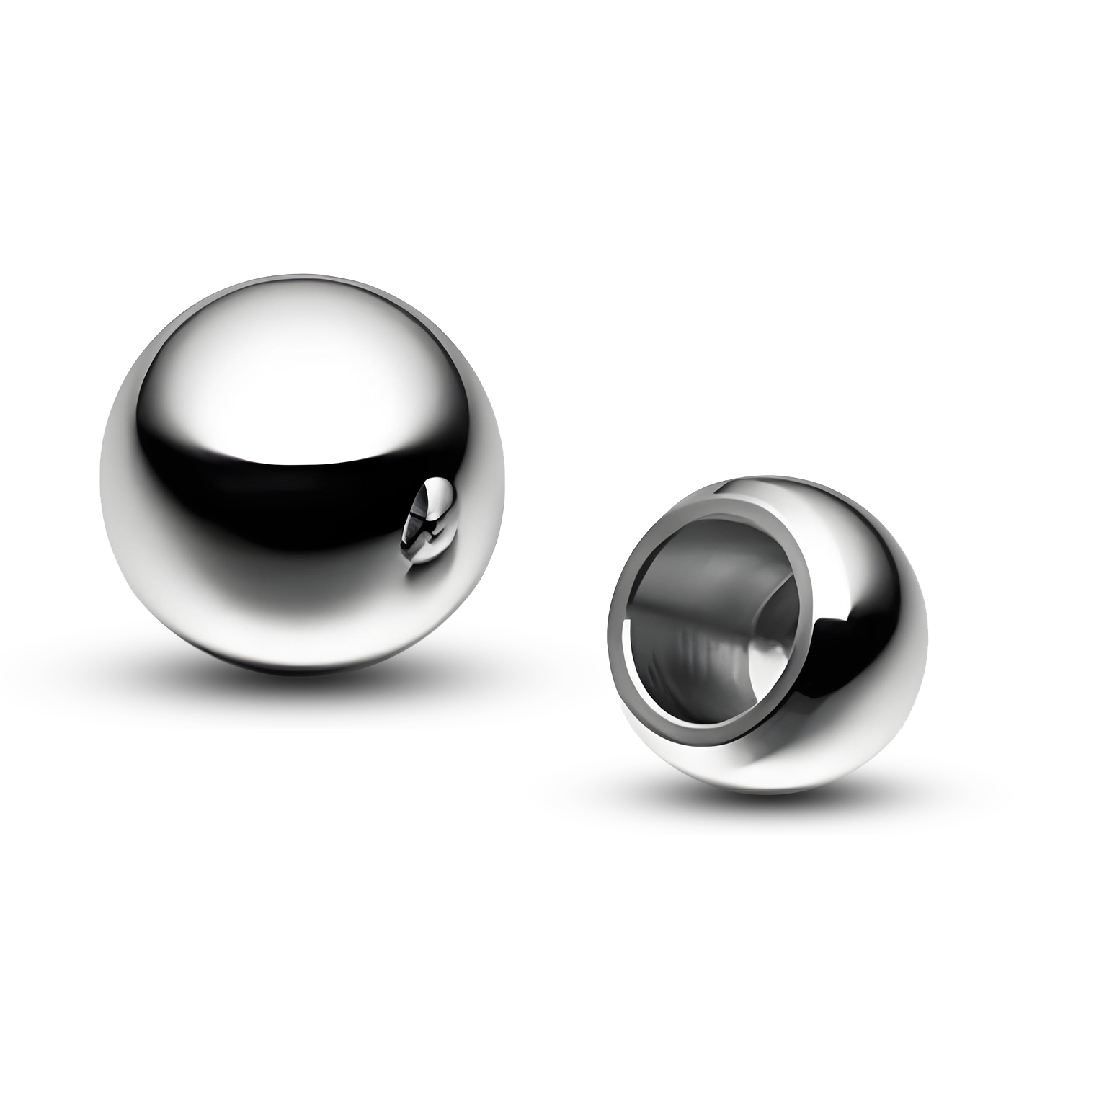

Cabeça femoral Especificações

| Materiais | Cobalto Chrome Molibdênio Liga | Modelo | H5C00 | |||

| Cobalto cromo molibdênio liga-fundição | 22/M | 23/L | 29/S | 28/M | 28/L | 29/XL |

| 0 | +3.5 | -3.5 | 0 | +3.5 | +7 |

| Materiais | Balt Chrome Molibdênio Liga | Modelo | H1C00 | |||

| Cobalto cromo molibdênio liga-fundição | CoΦ 22/0 | Φ 22/ 4 | Φ 28/-4 | Φ 28/0 | Φ 28/ 4 | Φ 28/ 8 |